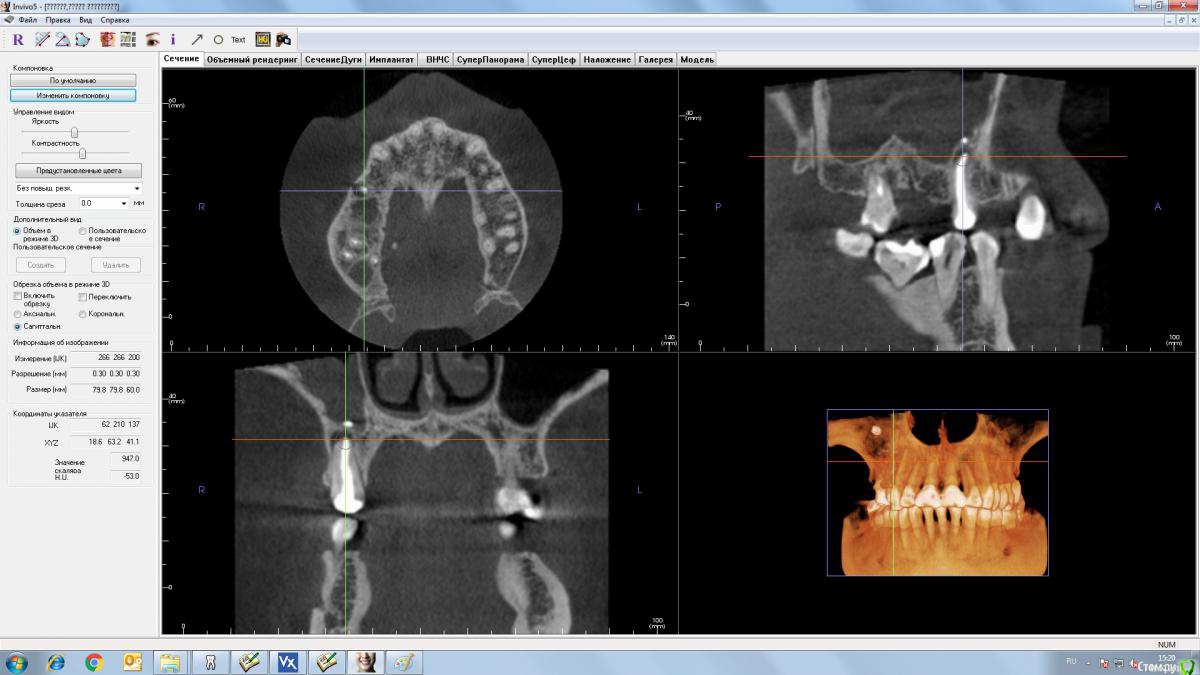

TIGER Опубликовано 19 июля, 2016 Поделиться Опубликовано 19 июля, 2016 1 вариант...там грибы в пазухе Ссылка на комментарий

Slaggy Опубликовано 19 июля, 2016 Поделиться Опубликовано 19 июля, 2016 Уважаемые коллеги, хотел бы получить совет и ваше мнение, как на данную ситуацию. Пациент изначально отказался от ортодонтического лечения. По плану:1. вариантвизит ЛОР, ( какие ждут пациента манипуляции???)после чего удаление 15, 17 зубов, возможно закрытие ороантрального соустья.Через 6 месяцев имплантация и далее все по плану. 2 вариант.Была мысль поставить 14, 16 (с закрытым синусом) импланты, провизорную конструкцию, через 3 недели удаление 15, 17.Через 6 месяцев установка 15,17 импланты. Смущает только возможность обострения 15 и 17 зубов после имплантации 14,16.Так как я относительно молодой хирург-имплантолог, прошу совета, может есть какие-то другие варианты.И хотелось бы узнать, если мы будем двигаться по первому плану, то какую конструкцию в качестве временной можно использовать? Точнее лучше использовать.А на какие риски готовы пойти? Если грибы - может получиться epic failИМХО - Вероятно грибы. Лор с эндоскопом - обязательно. Лечение пазухи санация зубов, 2-3 месяца пауза. Контрольное КТ, принятие решения о лифтинге и имплантации. Ссылка на комментарий